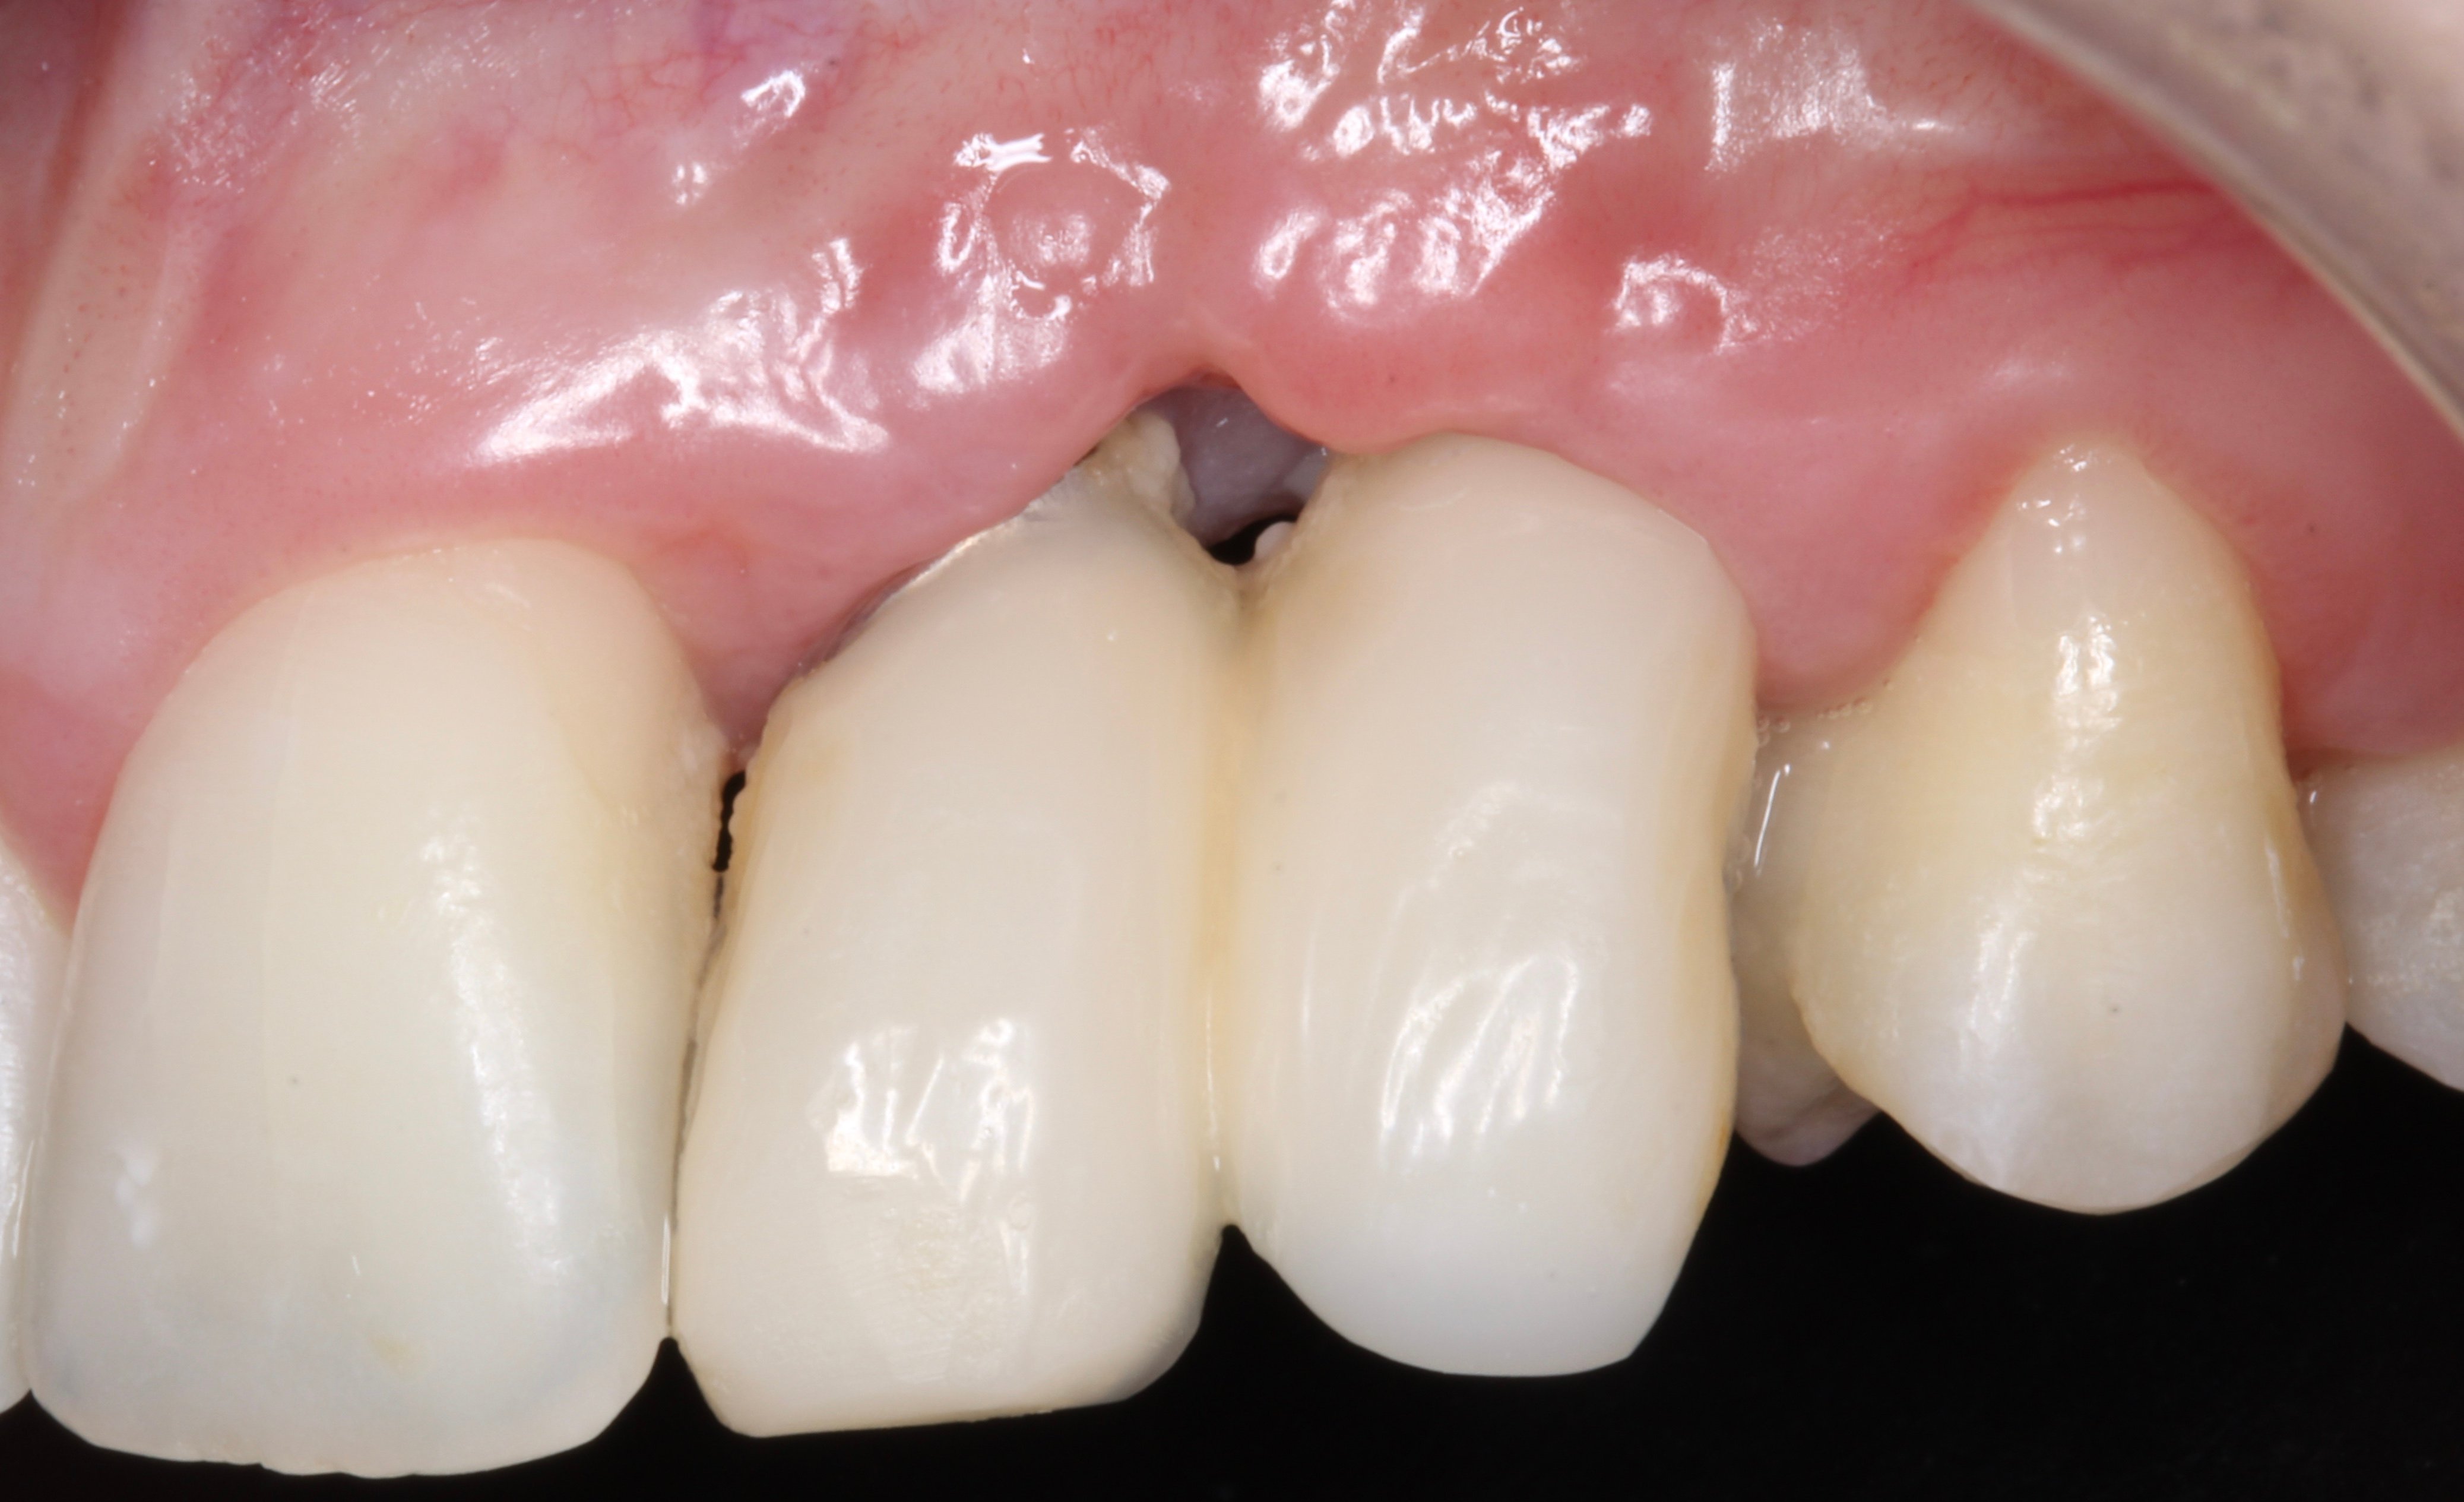

- 4 years later: Clinical and Radiographic Evolution of the Aesthetic Zone.

3D guided bone regeneration using an e-PTFE, Ti-reinforced NeoGen® membrane and 100% autogenous bone is a fully predictable treatment for the severe hard and soft tissue atrophy on the Aesthetic Zone. This statement is supported not only by panoramic and periapical x-rays, but also by CBCT sectional cuts where we can see the complete stability of the regenerated bone.